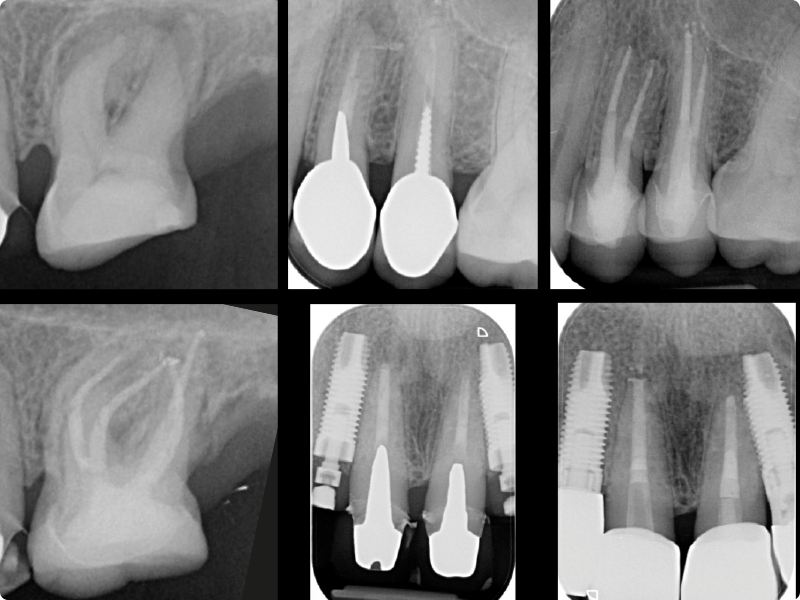

• Shaping calcified, curved and complex canals in primary treatments

• Very complex retreatments: protocols and clinical approach (Part 1)

• Very complex retreatments: protocols and clinical approach (Part 2)

• Altered anatomies and iatrogenic damage: operative protocols for managing root resorptions, perforations and large apical openings

• Removal of a fiber post

• Retreatment of the teeth obturated during the previous hands-on session

• Closure of a perforation and a large apical opening on 3D models replicating real clinical situations or on teeth provided by the participants